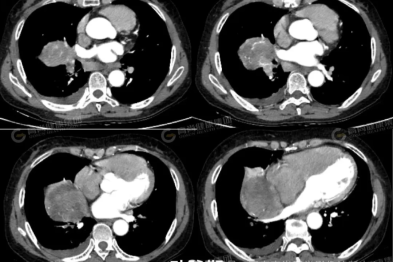

37 岁男子「身材修长」,心脏却是常人两倍大,元凶竟是这种罕见病